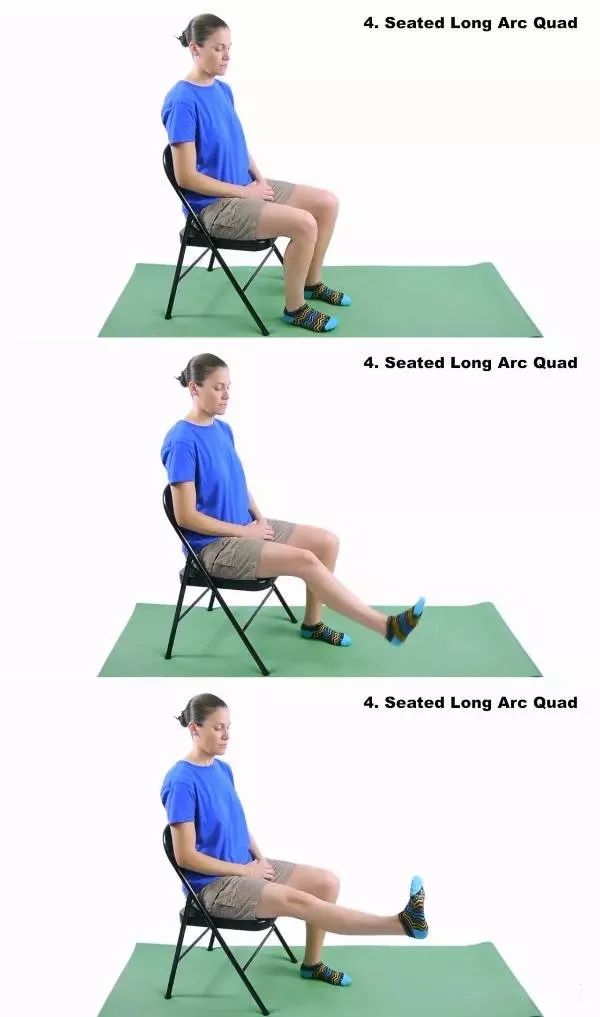

四

坐姿膝关节伸展练习

注意事项:

1、髌骨和脚趾垂直向上

2.将踝关节尽量向头部方向伸展(钩脚)

3.慢慢伸直膝关节,这个过程需要4秒以上

4. 大腿不要离开椅子

5. 保持5秒

6.慢慢放下,这个过程需要4秒以上